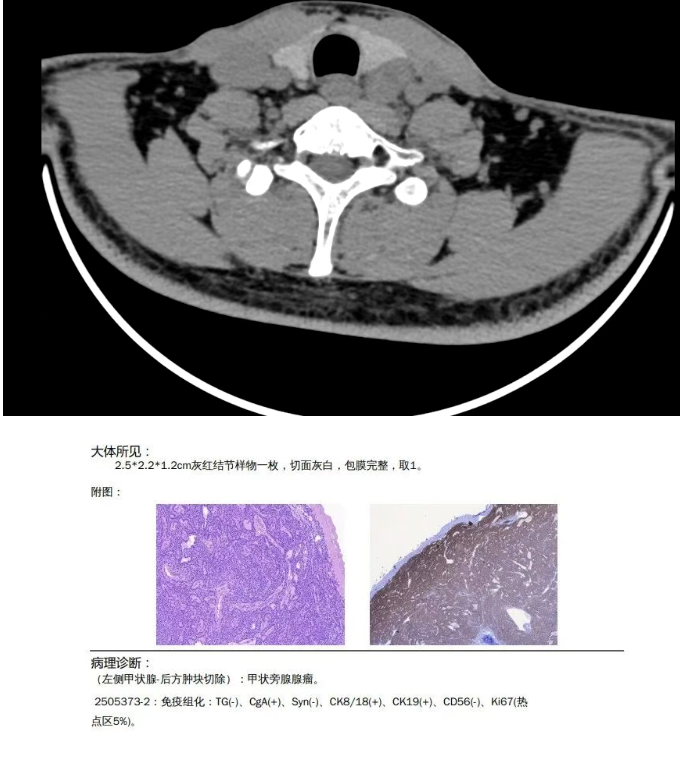

彩超、颈部CT下进行甲状旁腺肿瘤定位后,杨裕志主任带领手术团队进行甲状旁腺肿瘤切除术,术中30分钟内病理科快速冰冻切片提示病变为腺瘤,术后急查甲状旁腺激素 9.02(pg/ml),较手术前大幅下降,进一步明确诊断为甲状旁腺腺瘤引起甲状旁腺功能亢进。术后第二天复查:钙 2.57(mmol/L)、甲状旁腺激素 2.69(pg/ml),血钙已恢复正常。为应对甲状旁腺瘤切除后“骨饥饿综合征”导致血钙快速下降,预防性补钙;术后第五天复查,患者甲状旁腺激素逐步恢复至11.6(pg/ml)。